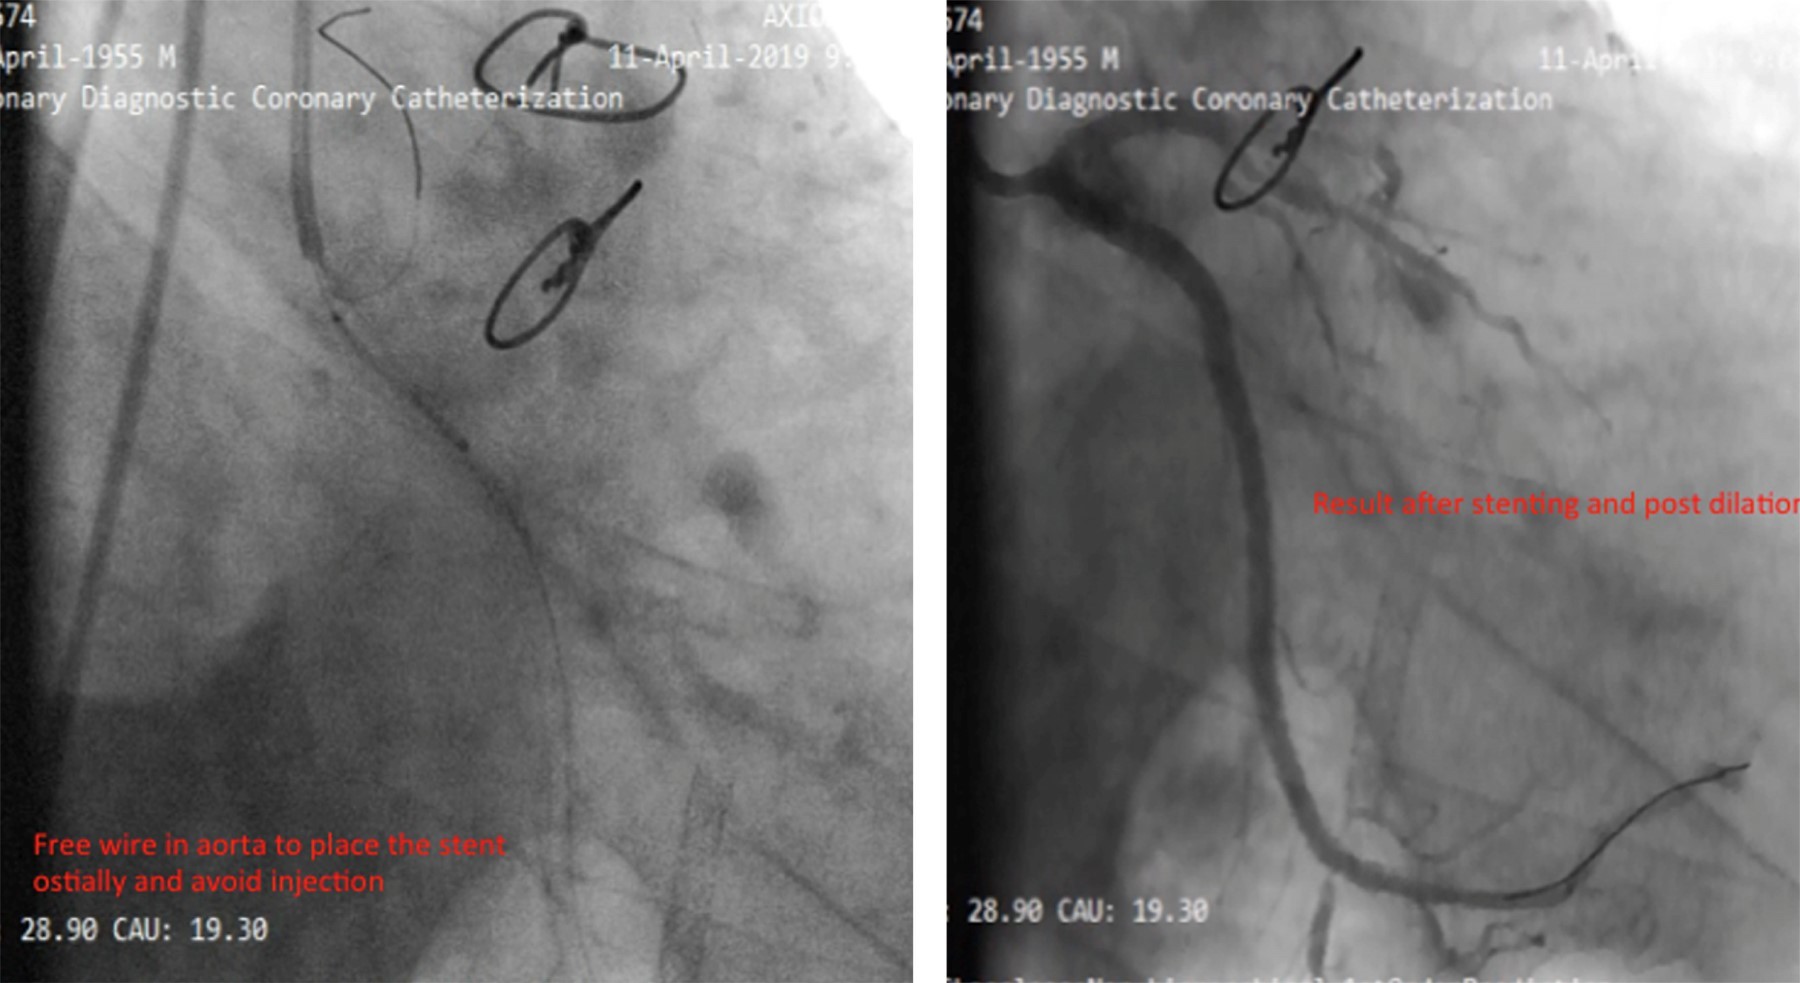

Reportamos el caso de un hombre de 78 años con antecedentes de cirugía de revascularización coronaria (CRC) e intervención coronaria percutánea (ICP) del injerto de vena safena (IVS) a la arteria marginal obtusa (MO). El paciente presentó síndrome coronario agudo y fue derivado a atención terciaria después de que la angiografía coronaria revelara reestenosis intrastent en una IVS trombótica, junto con oclusión total crónica (OTC) de la arteria circunfleja izquierda (CI). Nuestro plan inicial fue la intervención de IVS a MO debido a reestenosis del stent y trombosis. Durante el procedimiento, una rotura de balón resultó en disección y hematoma. Como intervención de rescate, se realizó stent nativo en la CI con OTC, seguido de oclusión con coil de la IVS. Surgieron complicaciones cuando el coil se desprendió y fragmentó, lo que llevó a la embolización de una partícula en la aorta descendente y la otra en la arteria femoral. Ambos fragmentos se recuperaron con éxito mediante un lazo. Este caso destaca la complejidad del manejo de las complicaciones de la ICP relacionadas con la IVS y la importancia de manipular cuidadosamente el dispositivo durante los procedimientos de colocación de la bobina.

Figura 1

Figura 2